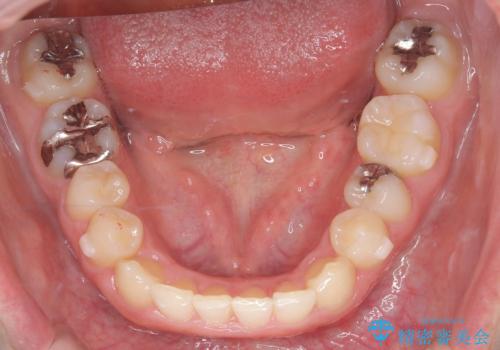

- 下の歯のがたつき(叢生)、真ん中(正中)が右にずれていることを主訴に来院されました。右上前から3番目の永久歯が埋まっている(埋伏)していることから正中は可能な限り合わせることをゴールとしてマウスピースでの矯正治療を選択しました。

今回の矯正治療では、透明なマウスピース型の装置インビザラインを使用しました。がたつきをとるため、安全性が確保できる範囲で歯と歯の間を少し削り必要なスペースを確保しました。